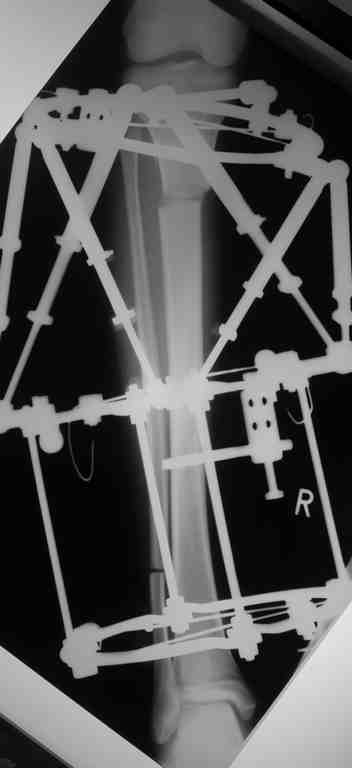

Выше представлены рентгенограммы открытого оскольчатого перелома нижней трети голени X-rays of Compound Comminuted # Distal/3 Lt Tibia

Операционные снимки перед и после наложения аппарата Илизарова In operation room before and after Ilizarov apparatus has been applied

Послеоперационные рентгенограммы Postoperative X-rays

В нижнем ряду представлены рентгенограммы после окончательной репозиции. And final reduction after Hexapod program has been finished